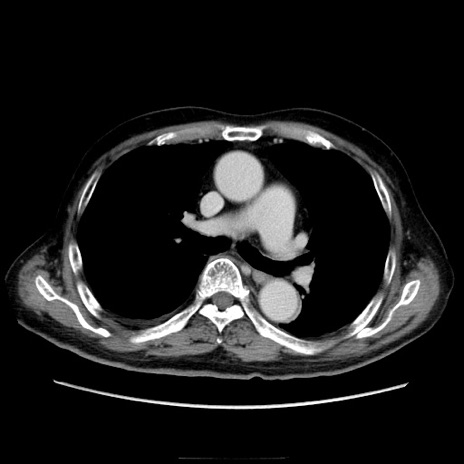

症例21(横断像)

【症例】70歳代男性

【主訴】腹痛

【現病歴】肝硬変・肝細胞癌にてかかりつけの方。約9時間前に食後より腹痛出現。症状が徐々に増悪し、嘔吐出現したため来院。

【既往歴】肝硬変、肝細胞癌(RFA、TACE後)

【身体所見】意識清明、表情苦悶様、BT 36℃、BP 129/78mmHg、P 88bpm、SpO2 97%(RA)、右上腹部から心窩部にかけて圧痛あり、反跳痛なし、筋性防御あり。

【データ】WBC 5800、CRP 0.16